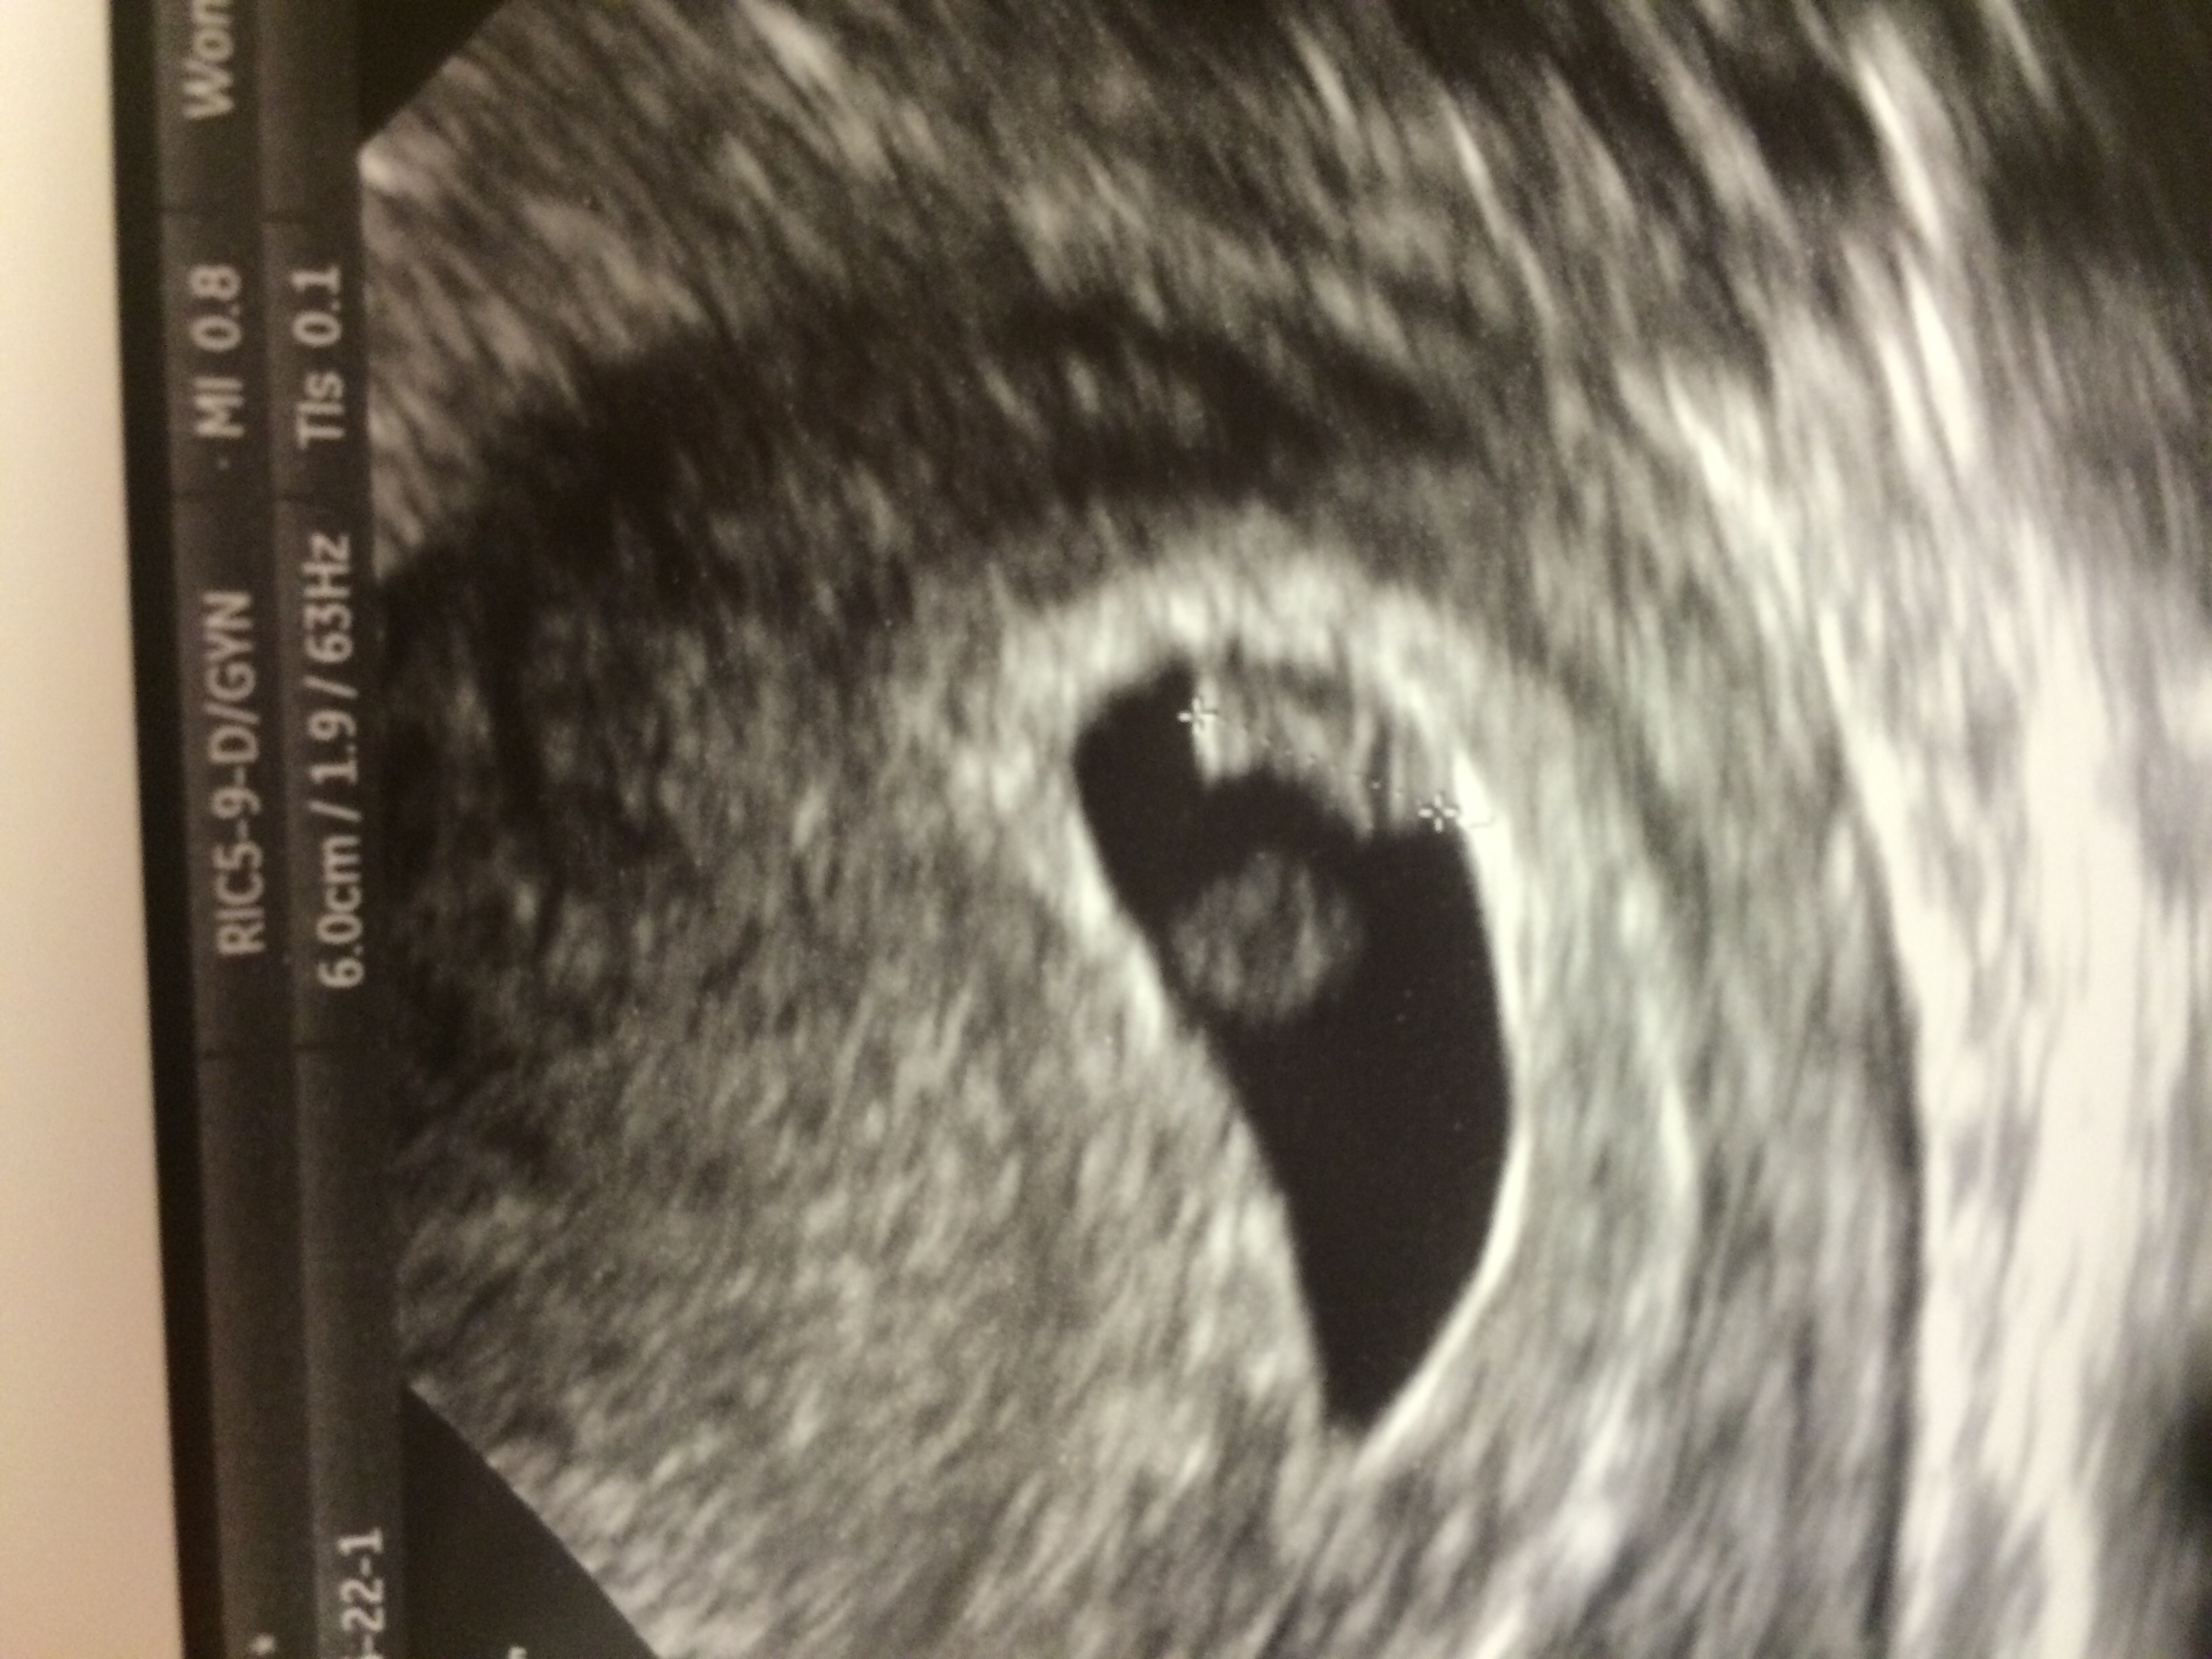

EDD: 15th Feb 2016

125 bpm

Thought i was further along.. Had a early scan because i had an mc 2 months ago.

Next week follow up to see if she/he has grown. Nervous!